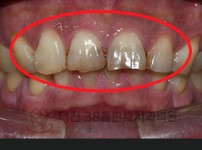

치료전후